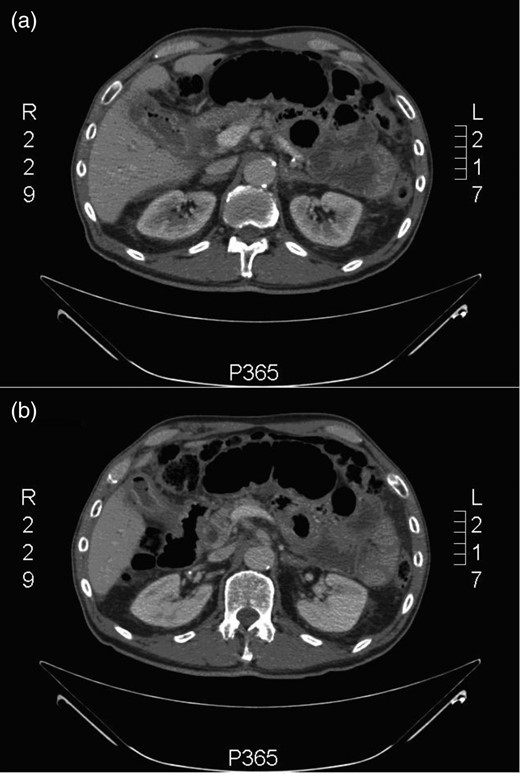

His blood on admission showed a raised white cell count of 12.5 × 103 cells/ml (with neutrophilia) and a C-reactive protein of 14.0 mg/l. His alanine transaminase was mildly raised at 79 U/l; however, his remaining liver and renal function tests were normal. His abdominal X-ray showed dilated loops of small bowel but no evidence of large bowel dilatation (Fig. 1). A provisional diagnosis of small bowel obstruction was made and a computerised tomography (CT) scan of the abdomen and pelvis was ordered. The CT showed multiple dilated loops of small bowel but no focus of obstruction (Fig. 2a). The gallbladder wall was thickened and oedematous and there was also evidence of gas within its lumen. Air was seen under the left lobe of the liver, suggestive of a bowel perforation. Furthermore, in Fig. 2b, the second part of the duodenum appears to be adherent and in communication to the gallbladder. Putting all these findings together, the radiologist felt that there was acute cholecystitis leading to a duodenal perforation and paralytic ileus.

CT abdomen + pelvis: (a) inflammation of the gallbladder and (b) a very closely adherent gallbladder to the second part of the duodenum (D2).